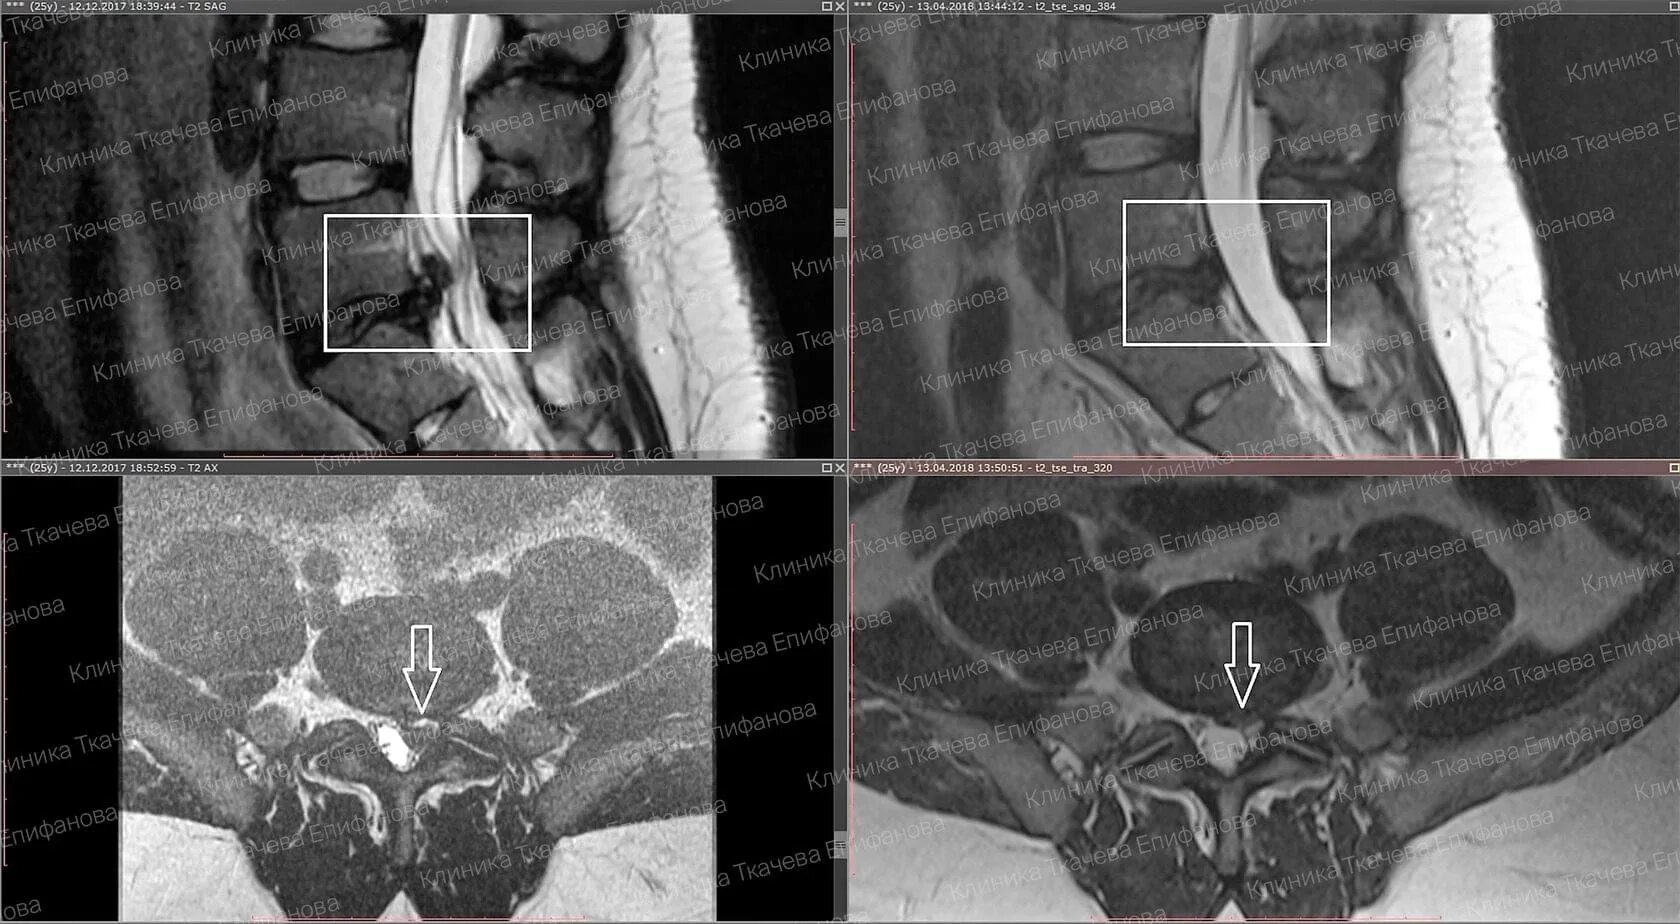

Что такое резорбция грыжи позвоночника